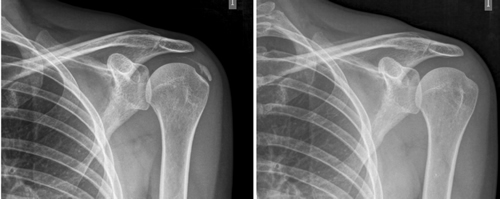

Figura 2